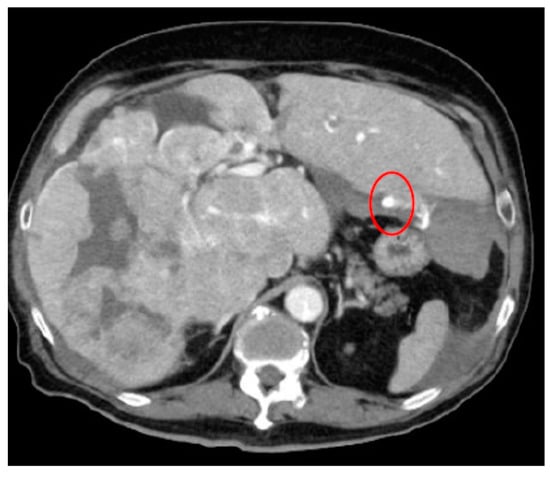

- AI for Image Analysis: AI-based image analysis algorithms can enhance the detection and diagnosis of extravasation events in imaging studies, such as ultrasound, MRI, and CT. These algorithms can automatically identify subtle signs of extravasation, assist healthcare providers in interpreting the imaging findings, and facilitate a timely intervention. This suggestion is subsequently extended as a separate discussion.